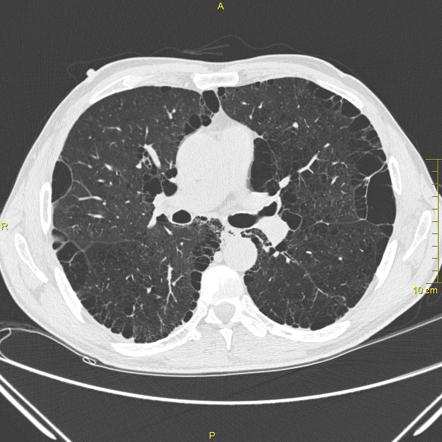

最近两年我深切地感受到,体检或者入院后胸部 CT 发现肺部结节的人越发多了起来,来问我结节要不要紧的同学也有好几个。如果没有任何呼吸道的症状,只是单纯体检做 CT 发现了肺部有小结节,需要注意一下报告对结节大小和影像特点的描述,比如直径有多大,是单个还是多个,是实性结节还是磨玻璃结节。

如果是实性结节,直径4mm 以下的,如果没有上述肺癌的高危因素,则不需要随访,有危险因素的每年复查一次 CT;结节直径 6-8mm 者应在6-12 个月之间复查, 如未发生变化,则在 18-24 个月之间 再次随访,其后转为常规年度检查;结节直径≥ 8mm,建议去看胸外科门诊,这时候需要医生结合结节的其他特征进行恶性肿瘤的概率预测,有的可能需要做 PET-CT,有的可能需要手术活检明确。

如果是磨玻璃结节,则要更谨慎一点,因为所谓的磨玻璃影指的是结节密度不均匀,结节内有很多血管和气管的影像,而疯长是癌症的特点,「兵马未动,粮草先行」,疯长所需的营养依赖增生的血管提供。因此,如果是单个纯磨玻璃结节,<5mm 的话,建议 6 个月后复查胸部CT,随后行胸部 CT 年度随访;≥ 5mm 的话,建议 3 个月随访胸部 CT,如果没有变化的话随后可进行胸部 CT 年度随访;如果直径超过 10 mm,去看胸外科门诊,需非手术活检和(或)手术切除。

如果是混合的结节,单个直径 ≤ 8mm 者建议在 3、6、12 和 24 个月进行 CT 随访,无变化者随后转为常规年度复查;直径 >8 mm,还是去看呼吸科或者胸外科,是经验性抗感染治疗、穿刺活检还是手术,交给专科医生来判断。

来源:Case Report: Do we really care about incidental lung nodules?

上图是典型的肺部结节在胸部 CT 随访中的进展。胸部 CT 扫描(2012 年)显示,右肺黄圈处有一个界限分明的小肺结节;随后的胸部 CT 扫描随访(2014、2015 年)显示右中叶肺结节明显逐渐增大;右下图是右中叶肺结节的 PET-CT 图像。